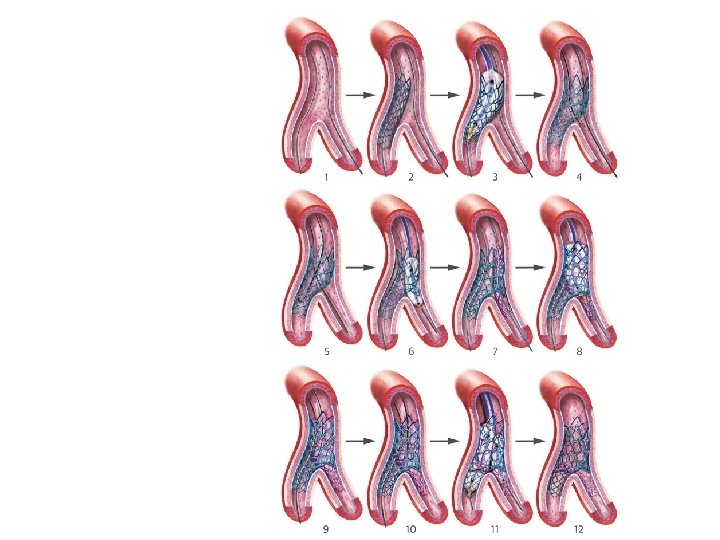

DK crush

� immediate patency of both branches is assured &therefore it should be applied in conditions of instability or when the anatomy appears complex. � should be avoided in wide angle bifurcations. � Only SBhas to be re-wired ¬ both branches as in culotte technique. � The crush technique has evolved and is nowadays performed with less stent • protrusion into the MB(i. e. , mini-crush) &mandatory 2 -step FKI. � crush” technique can therefore be considered as a sort of simplified “culottes” technique � The mini-crush may be associated with more complete endothelialisation and • easier re-crossing of the crushed stent.